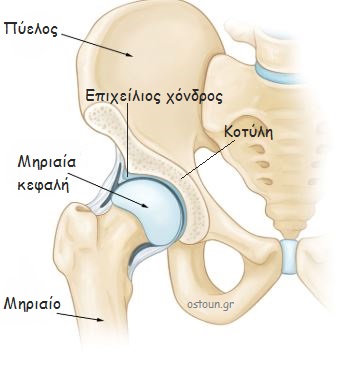

Λίγα λόγια για την ανατομία

Το ισχίο αποτελείται από την κοτύλη και την κεφαλή του μηριαίου. Η κοτύλη είναι τμήμα του οστού της λεκάνης και η κεφαλή του μηριαίου είναι το εγγύς τμήμα του μηριαίου οστού.

Η επιφάνεια επαφής των δύο οστών καλύπτεται από αρθρικό χόνδρο. Ο χόνδρος επιτρέπει στα δύο οστά να κινούνται με χαμηλό συντελεστή τριβής. Γύρω από την κοτύλη υπάρχει ο επιχείλιος χόνδρος, ο οποίος αυξάνει τη σφαιρικότητα της κοτύλης. Ως αποτέλεσμα, αυξάνεται η σταθερότητα της άρθρωσης.